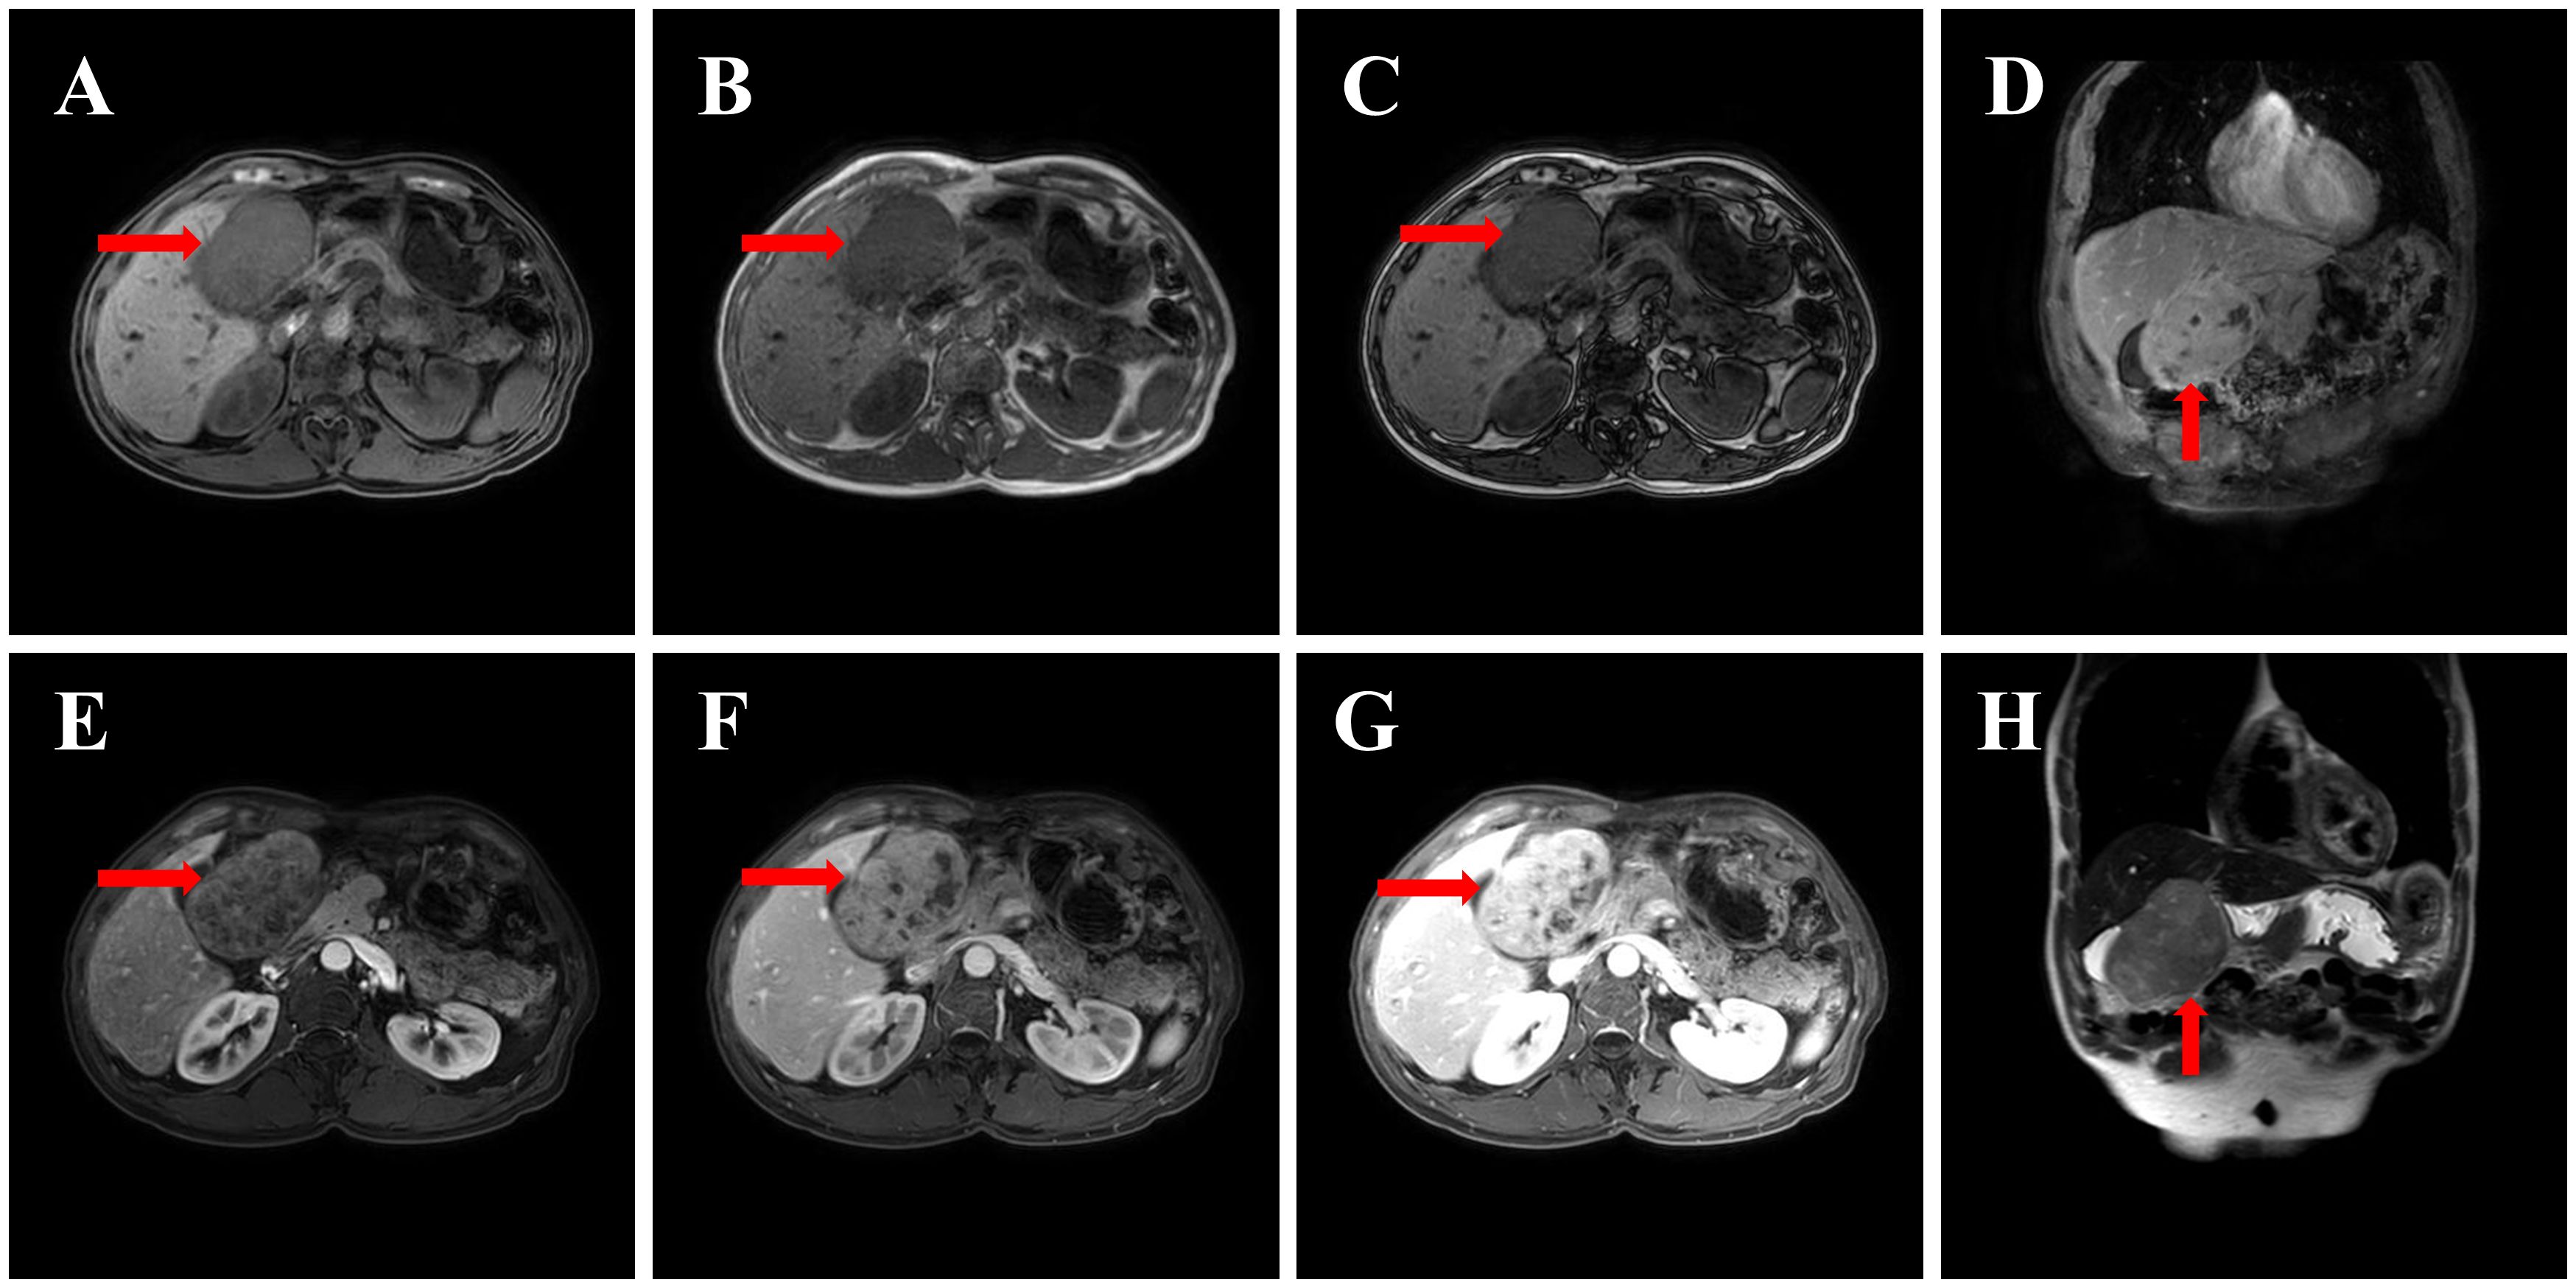

Background: Primary hepatic leiomyosarcoma (PHL) is an extremely rare malignancy often misdiagnosed due to nonspecific imaging features overlapping with cholangiocarcinoma. This case highlights diagnostic challenges and the potential association of SDHB positivity with PHL prognosis. Case Presentation: A middle-aged male presented with an asymptomatic liver mass. Preoperative CT/MRI revealed a 10-cm lesion with progressive heterogeneous enhancement and delayed capsular enhancement, initially diagnosed as cholangiocarcinoma. Left hepatic lobectomy confirmed PHL. Immunohistochemistry showed SDHB positivity and low Ki67 (15%). The patient recovered well with no recurrence at 6-month follow-up. Conclusions: PHL can radiologically mimic cholangiocarcinoma, necessitating inclusion in differential diagnoses for "cholangiocarcinoma-like" liver masses. SDHB positivity may indicate favorable tumor biology, but further studies are needed to validate its prognostic value. Surgical resection remains curative for localized PHL.